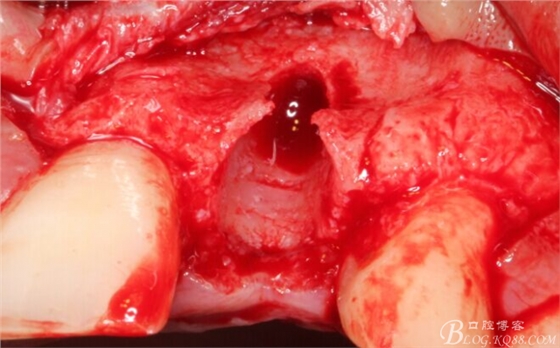

再次翻瓣。

先行粘骨膜減張,取自體血液。

根方用取骨鉆取自體骨。